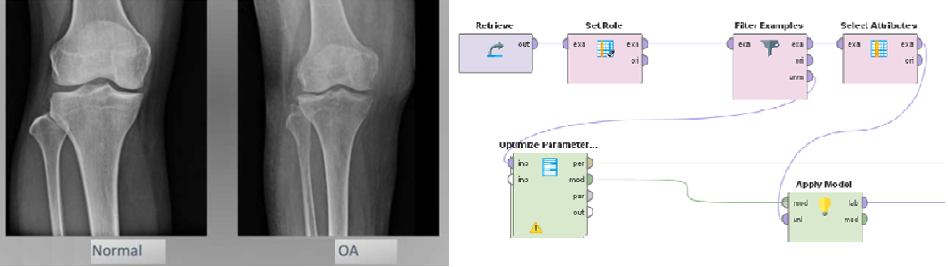

• Used RapidMiner to build an AI prediction model capable of forecasting joint deterioration over the next 2 and 3 years.

• Used RapidMiner and the Naive Bayes method to build a prediction model for the progression of osteoarthritis.

• Based on validation results, the model achieved an accuracy of around 80% when predicting disease progression over the next 2 and 3 years.